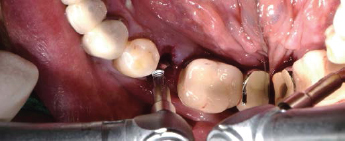

술전

Volume Up Gauge로 직경 확인 (Ø8.5)